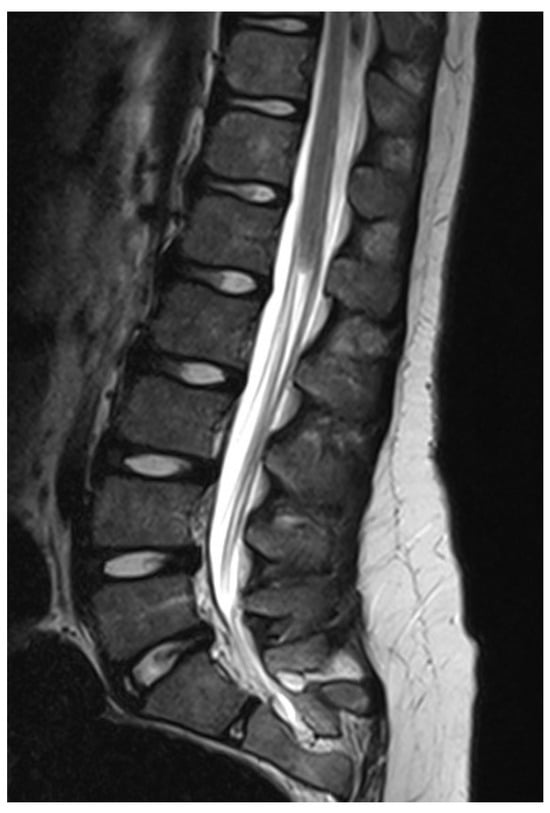

Figure 8. LDM is formed by neural tissue that is tethered toward the extraspinal mesodermal tissues. Note the deformed dorsal aspect of the spinal cord at the level of the dysraphic lesion (white arrow), which can be located at any level of the spinal cord.